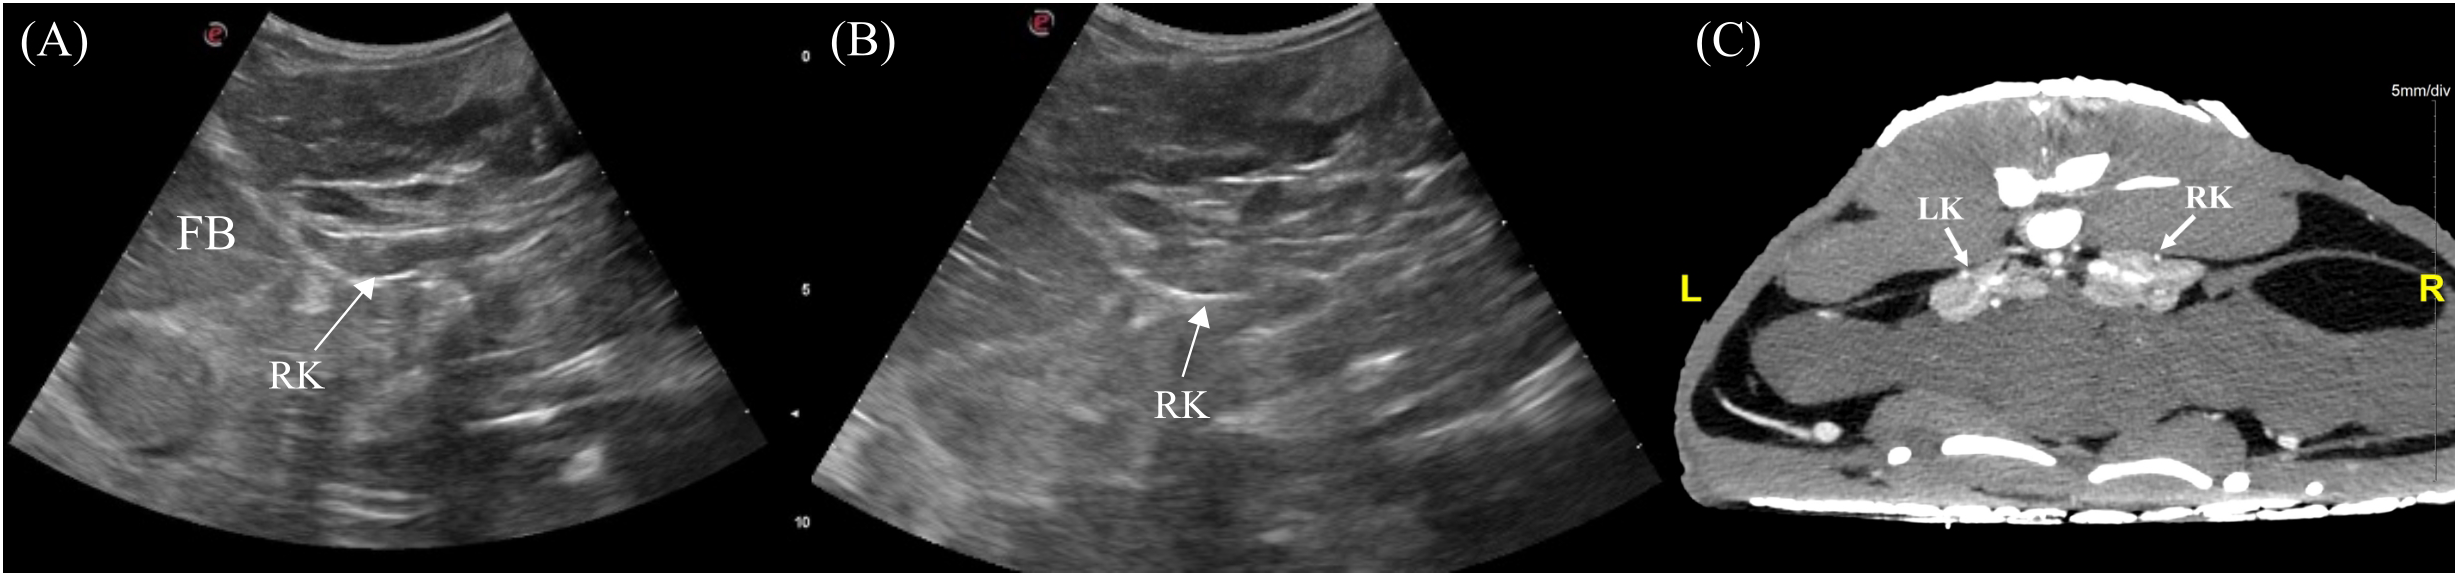

3.3.8 Kidneys

The left and right kidneys were identified 3/7 and 5/7 animals respectively. The kidneys were positioned in the caudodorsal coelom parasagitally extending into the pelvic canal (Figure 4). To visualize them, the transducer was placed dorsolaterally on the lateral flanks just cranial to the pelvic (Figure 3, transducer positions 5 and 9). In the longitudinal view, the kidney was irregularly elongated with tapered ends whereas in transverse the kidney had an irregular ‘flower-like’ shape (Figure 13). The kidney parenchyma was homogenous with slightly coarse echotexture and isoechoic to adjacent musculature with hyperechoic rim and hilum. Vascularity was poorly detected using Doppler.

Figure 13

Ultrasonographic appearance of the right kidney in (A) sagittal and (B) transverse views and (C) transverse view of CT image of the kidneys in Alligator sinensis. [FB, fat body; LK, left kidney; RK, right kidney].